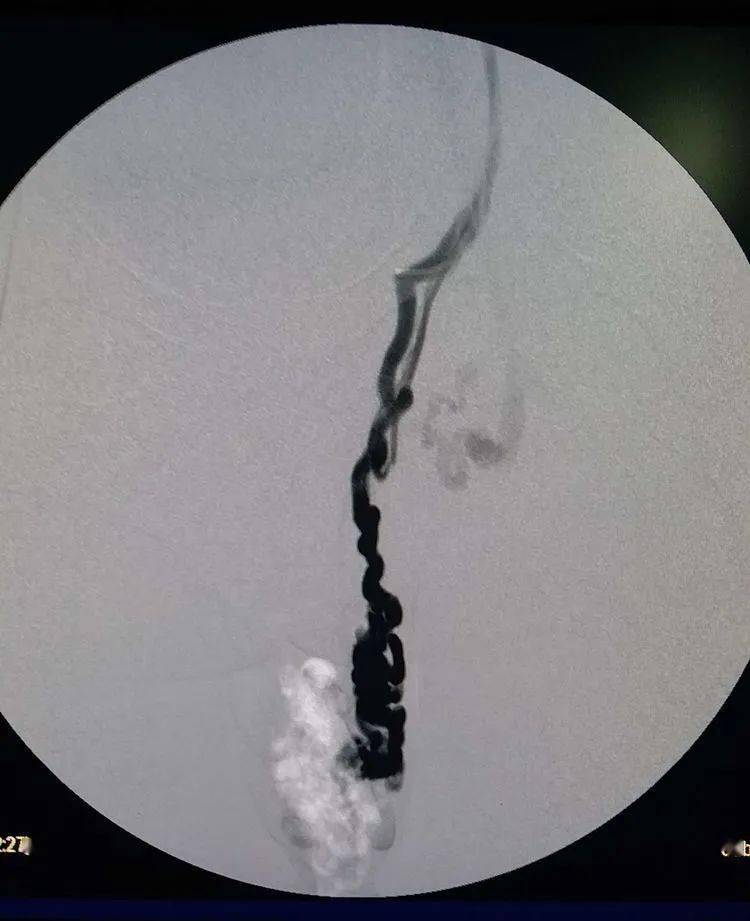

股静脉入路,选入左侧生殖静脉造影!可以发现精索静脉曲张

精索静脉曲张泡沫硬化剂栓塞术及术后随访情况